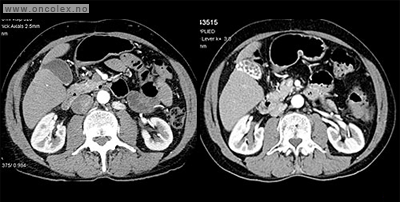

Bildeeksempler